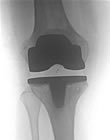

Endoprothetik

Endoprothesen sind künstliche Gelenke, mit denen ein abgenutztes oder unfallbedingt geschädigtes Gelenk ersetzt werden kann. Am häufigsten implantiert werden von uns Endoprothesen des Hüftgelenkes, gefolgt von Kniegelenk- und Schulterendoprothesen.

Endoprothesen bestehen in der Regel aus gut körperverträglichem Metall (meist Titan) und einem Spezialkunststoff. Die Metall-Kunststoff-Kombination hat einen sehr geringen Reibungskoeffizienten und ist sozusagen „selbstschmierend“.

Durch ein spezielles Oberflächendesign und genaue Einpassung können zementfreie Endoprothesen in der Regel ohne zusätzliche Hilfsmittel im Knochen verankert werden. Die endgültige Festigkeit entsteht dann durch knöcherne Umbauvorgänge nach der Operation. Der Knochen „verwächst“ mit der Prothese.

Mit der Verwendung von Knochenzement ist von Anfang an eine vollständig belastungsstabile Verankerung der Endoprothese möglich. Dafür hat Knochenzement den Nachteil, dass selten Unverträglichkeitsreaktionen möglich sind und dass die Haltbarkeit gegenüber zementfrei verankerten Endoprothesen in der Regel etwas geringer ist.